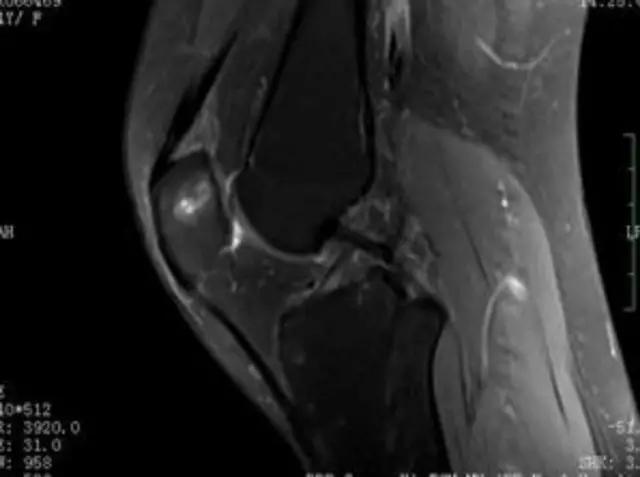

下图是同一个病人的MRI照片,MRI显示的内容更多,包括骨与软组织等,很多早期的、细微的病变都能清晰显示,其诊断报告对病人造成的影响也更大!

地中海贫血与白血病均为血液系统的问题,主要表现在骨髓,疾病的发病机理有别,MRI表现也不相同;我们可能不是很熟悉这些疾病,也能够从MRI发现区别。图1:正常膝关节 图2:地中海贫血 图3:白血病

我们可能都不熟悉T1、T2,怎么办?当我们发现有问题后,利用照片上图像的对比,推测病变的可能也是一种诊断方法。病例:黄XX,女,39岁,左膝关节反复交锁1年。图1:肿物信号与骨信号一样图2:肿物信号与骨信号一样图3:肿物信号与骨信号不一样 肿物应该与骨相关,但不是骨性,推断:膝关节滑膜软骨瘤。手术后得到证实。